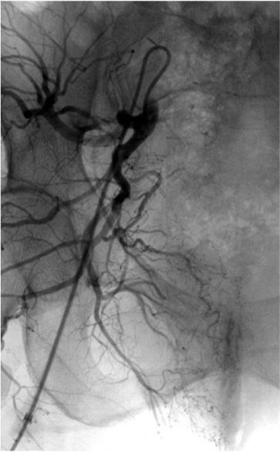

I 型 选择性直肠上动脉造影动脉早期 |

I 型 直肠上动脉造影 动脉末期 |

直肠上动脉造影实质期,没有明显异常发现 |

左右直肠上动脉很容易栓塞 |

左右直肠上动脉栓塞后造影 |